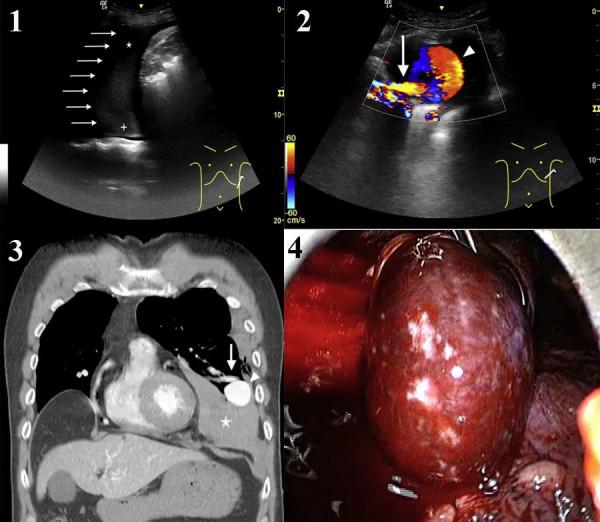

左側胸部的床旁超聲提示胸膜腔積液(圖1)。

彩色多普勒顯示動脈瘤病變伴供血動脈(圖2)。

胸部CT證實診斷為左肺動靜脈畸形伴大量左側血胸(圖3)。

急診胸腔鏡見胸腔內有不凝血及血凝塊800 ml,可及一直徑5 cm血管瘤,表面破潰,有活動性出血(圖4)。